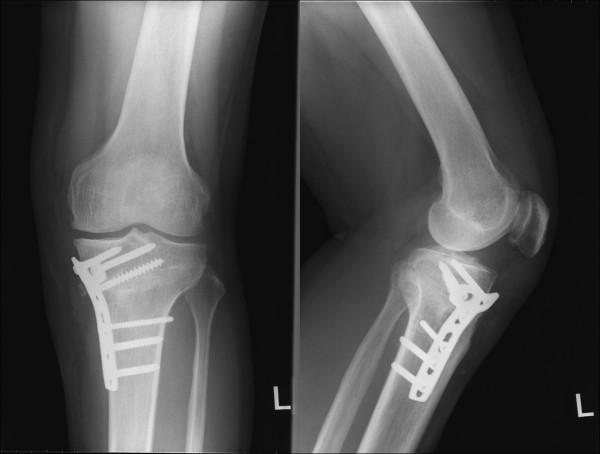

A 40 year old welder who underwent opening-wedge high tibial osteotomy for correction of alignment in a varus knee developed persistent pain with loss of knee extension. The posterior tibial slope increased from 9 degrees to 20 degrees after the osteotomy and caused the anteromedial knee pain and limited extension. The patient then underwent a revision osteotomy using a closing wedge technique to correct tibial slope. The osteotomy was performed, first from the medial cortex in the lateral direction, and second in the anteroposterior direction to remove the tibial bone in wedge shape and obtain full extension of the knee. The posterior tibial slope decreased to 8 degrees after the revision osteotomy and the patients returned to pain-free daily life. We reviewed this unique technique for correction of sagittal malalignment using a closing-wedge osteotomy for revision after opening-wedge osteotomy.

一名40岁的焊工因膝内翻接受了开放性楔形高位胫骨截骨术以矫正力线,术后出现持续疼痛且膝关节伸展受限。截骨术后胫骨后倾角度从9度增加到20度,导致膝关节前内侧疼痛和伸展受限。该患者随后采用闭合楔形技术进行翻修截骨术以矫正胫骨倾斜度。截骨术首先从内侧皮质向外侧进行,然后从前向后进行,以楔形切除胫骨骨质,使膝关节完全伸直。翻修截骨术后胫骨后倾角度降至8度,患者恢复了无痛的日常生活。我们回顾了这种使用闭合楔形截骨术矫正矢状面畸形的独特技术,用于开放性楔形截骨术后的翻修。